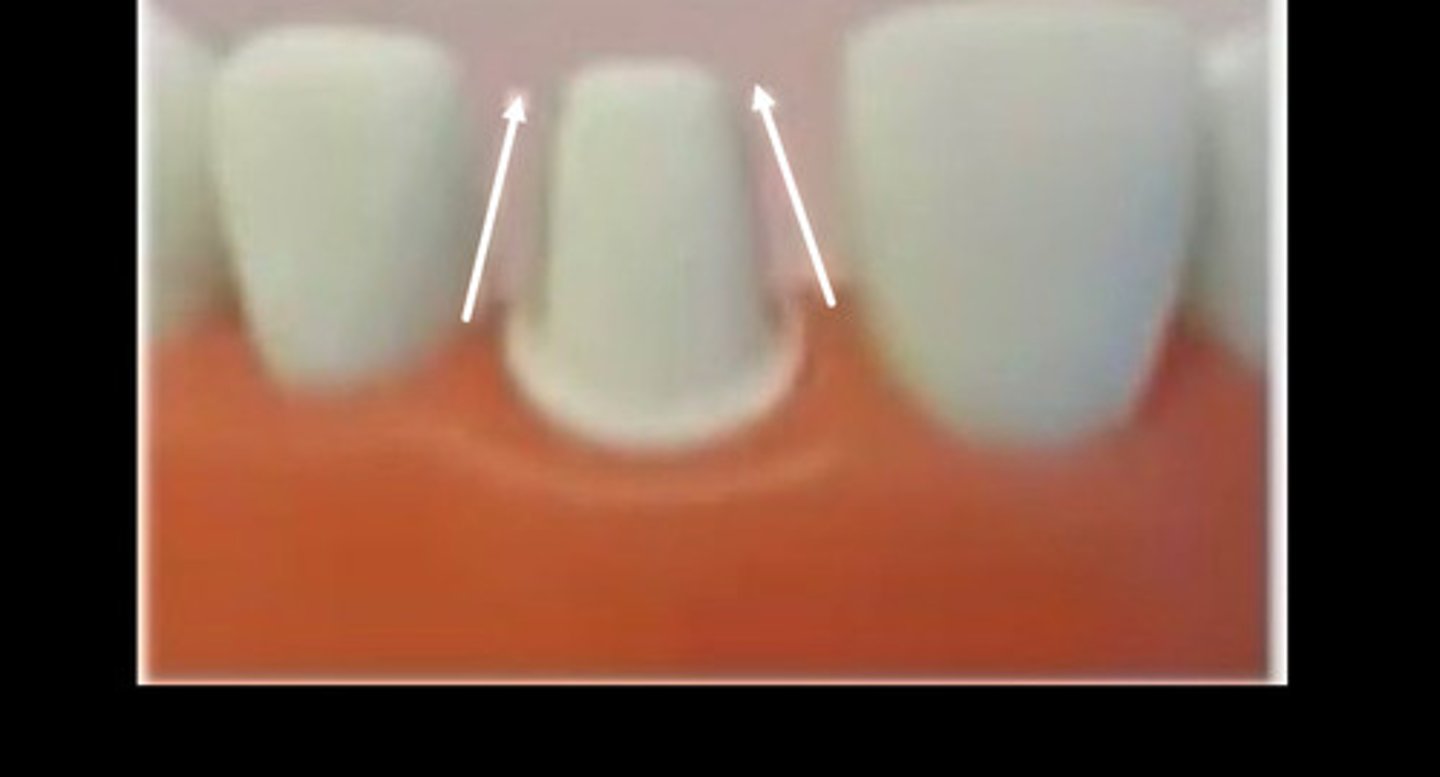

Black

J lip

Blue

Margins more than 0.5mm above gum

Red

End cutting bur

Fix j lip with